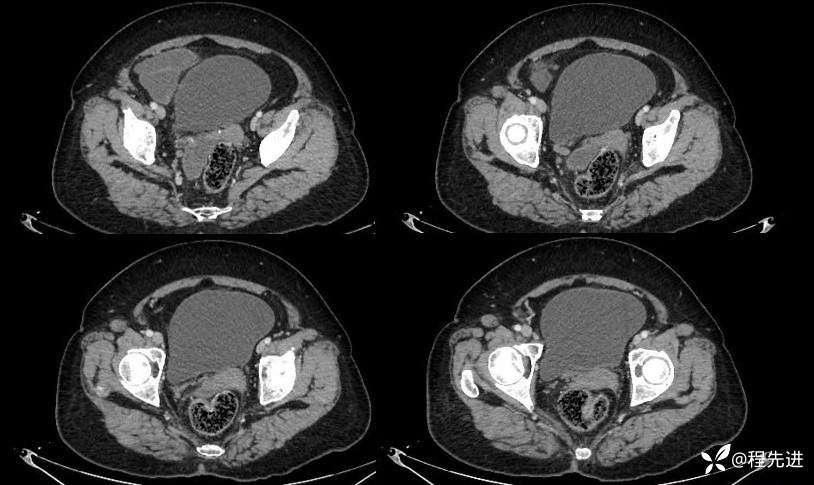

动脉期:

门脉期: